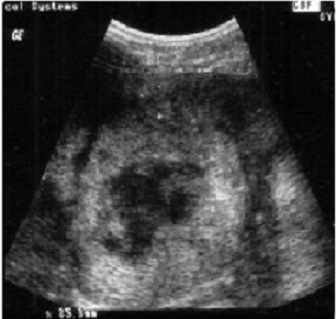

Image echographique du metastase hepatique :

Aspect est variable , souvent multiple a des nodules hypo ,

isoechogene avec contour de hypoechogene , parfoie est

hyperechogene

Aspect hypoechogen des

metastases cancereuse du foie |

Aspect de reverse

hyperchogene des metastases du foie |